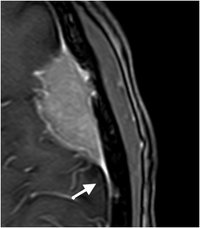

Meningeom - T1 mit KM

Konvexitätsmeningeom mit charakteristischem "dura tail".